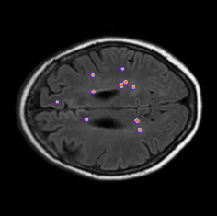

Qualitative evaluation

Qualitative results are depicted in Fig. 4. Inspecting these results visually, we can observe that there are two major types of improvements when employing the proposed boundary loss. First, as the methods based on DSC losses, such as GDL, do not use spatial information, prediction errors are treated equally. This means that the errors for pixels/voxels in an already detected object have the same importance as the errors produced in completely missed objects. On the contrary, as our boundary loss is based on the distance map from the ground-truth boundary , it will penalize much more such cases, helping to recover small and far regions. This effect is best illustrated in Fig. 1 and Fig. 4 (third row). False positives (first row in Fig. 4) will be far away from the closest foreground, getting a much higher penalty than with the GDL alone. This helps in reducing the number of false positives. Additional qualitative results for other base losses, and their combination with the proposed boundary loss, are depicted in Figures 5, 6. These figures also show failure cases (last column) of the boundary loss.